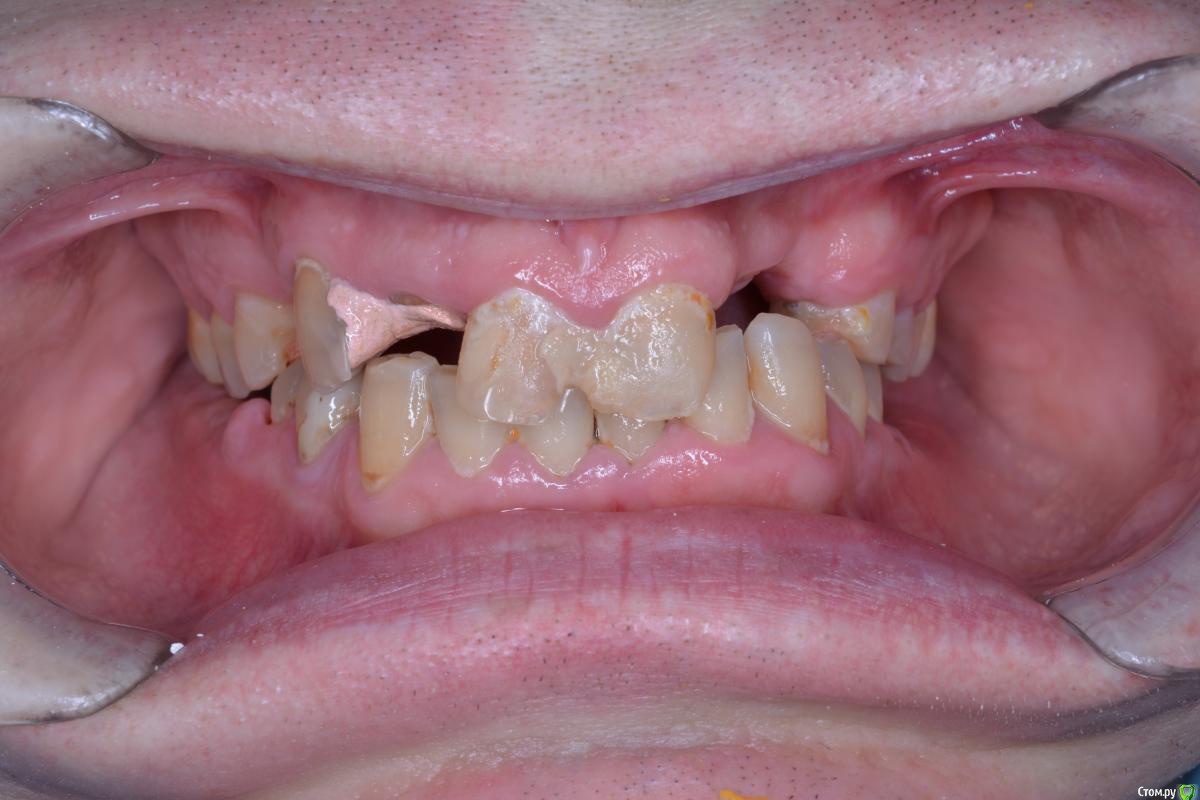

alekcandr ovs. Опубликовано 9 января, 2018 Поделиться Опубликовано 9 января, 2018 Пациент 43 года, очень боялся стоматологов и доболтаться до такого, с чего начать ???Мой предварительный план лечения депрограмация ,регистрация Ц.С, поднятие прикуса , Wax up ,хир.удлинение 1.1,1.6,1.7,2.1,2.4,2.5,2.6,2.7,имплантация 3,4 сегмент, тотал В.Ч, Н.Ч мостовидные протезы 1.5--1.3----1.1 2.1-------2.4,2.5.может искус.десна фронт !!!! 1. Вопрос чем лучше депрограмировать и найти Ц.С ????2.На сколь максимум можно удлинять моляры В.Ч ограничитель трифуркация ??? 3. Коллеги помогите сложный для меня случай!!! Всем добра Ссылка на комментарий